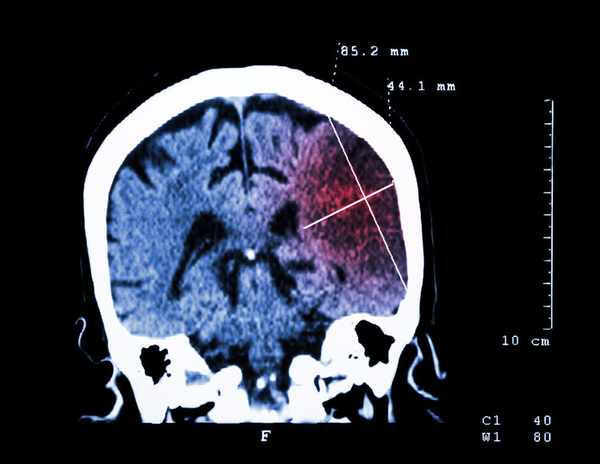

圖源:醫學界